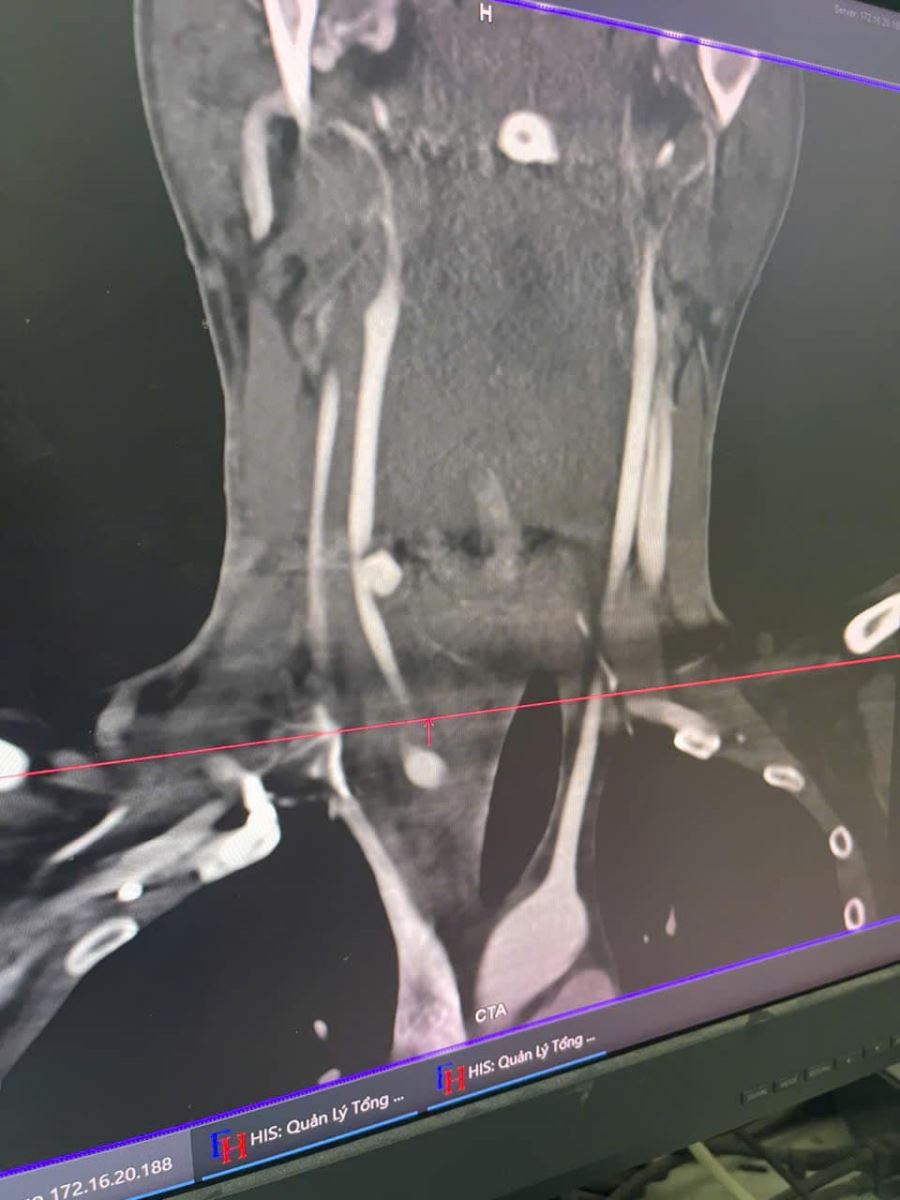

Khám cấp cứu ghi nhận : có dấu hiệu sốc mất máu; Vết thương: 2cm bên cổ phải, nghi ngờ đứt động mạch cảnh chung phải. Ngay khi tiếp nhận bệnh nhân, các bác sĩ tại khoa Cấp cứu lập tức kích hoạt báo động đỏ nội viện, huy động toàn bộ ekip đề điều trị bệnh nhân sớm nhất.

- Khâu nối động mạch cảnh chung bên phải.